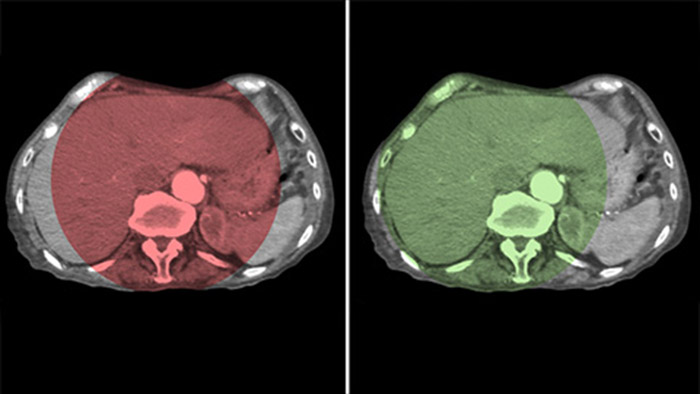

CBCT Dual ermöglicht die 3D-Erfassung einer arteriellen Phase zur Darstellung von Gefäßstrukturen und einer postarteriellen Phase zur Darstellung der Ansammlung von Kontrastmittel in einem automatisierten Schritt.5

Dual View ermöglicht die gleichzeitige Darstellung von zwei CBCT-Datensätzen. Sowohl die arterielle als auch die postarterielle Phase können nebeneinander oder in einer fusionierten Überlagerungsansicht angezeigt werden.